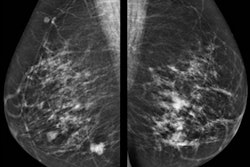

VIENNA - Mammography and ultrasound underestimate 30% of disease in patients with invasive ductal carcinoma (IDC), according to research from Israel presented at ECR 2018. MRI overestimates the extent of disease, but at least no cancer is left behind.

IDC constituted about 80% of the study group and ILC 20%, so the proportions mirrored the general population. The overall concordance rate for all three imaging modalities was relatively similar, between 65% and 75%, the researchers found. Most concordance cases had only unifocal disease, with a minority showing multifocal disease. Mammography and ultrasound tended to underestimate focality of disease, whereas MRI overestimated disease. The same was true regarding multicentricity in IDC, with an equal proportion of 76% concordance between all three imaging modalities. However, in the 25% discordance, mammography and ultrasound underestimated disease whereas MRI overestimated disease more commonly.

ILC told a different story: MRI demonstrated a much higher concordance compared with mammography and ultrasound. In mammography and ultrasound, the concordance rate was less than 50%.

"We were missing additional foci in over 50%," Sella said. "Regarding those cases with discordance, in MRI, of course, it was almost 90% concordance. Regarding cases with discordance, again mammography and ultrasound underestimated disease and discordance was very rare for MRI, so it doesn't really matter if it over- or underestimates."

In terms of multicentricity in ILC, the trend continued: Mammography and ultrasound underestimated disease extent and MRI overestimated it.

"The added benefit of MRI for evaluation of the extent of disease is clearly greater in ILC than IDC, demonstrating an 80% to 90% concordance rate with pathology," she said. "We suggest that MRI should routinely be included in preoperative evaluation of patients with ILC."